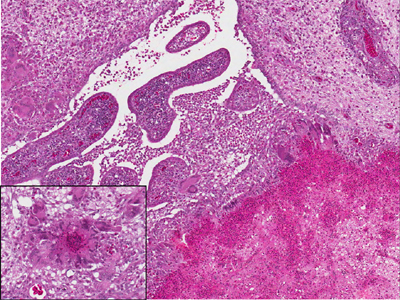

DACTYLARIOSIS: Tissue from a young turkey (X100; insert X400)

Description: Brain. Necrotic foci infiltrated by heterophils, macrophages and multinucleated giant cells, granulomatous ventriculitis, histiocytic and lymphocytic perivascular cuffing, gliosis, and neuropil edema.

Comment: hyphae are commonly invisible by H&E and specific stain (e.g., PAS, GMS) is required.

Morphologic diagnosis: Sever, multifocal, chronic granulomatous encephalitis

Etiologic Diagnosis: Ochroconis gallopavum (formerly Dactylaria gallopava)

Presumptive route of fungal infection: inhalation > hematogenous > choroid

Plexus > Ventricles > gray matter. Dr Z. Raviv